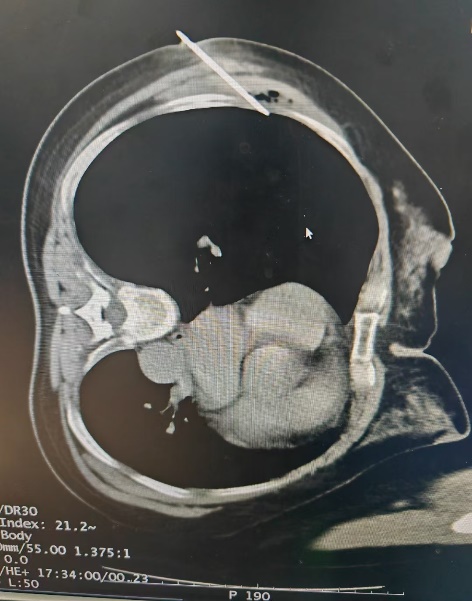

有一名女性患者,因咳嗽、咳痰40余天来院就诊,行胸部CT提示:右肺上叶病灶,不排除肺癌可能。为进一步明确诊断,予以充分评估后,在CT引导下行经皮肺穿刺活检术,病理结果显示:(右肺)肺泡上皮异型增生,局灶结构紊乱,考虑腺癌,建议免疫组化六项检查,为患者的后续精准治疗提供了依据。